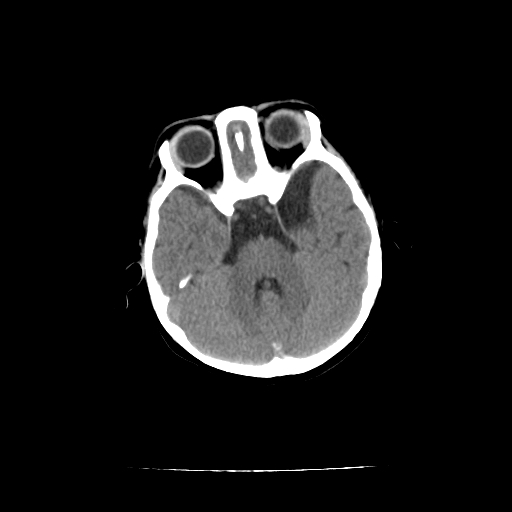

女,10个月,头外伤三天,伤后爱哭闹,吃奶少,睡觉不踏实。

左侧颞极蛛网膜囊肿

1)左侧颞极蛛网膜囊肿。2)第四脑室出血?

1、左侧颞极蛛网膜囊肿;2、第四脑室出血?3、右侧顶叶脑裂畸形伴灰质异位?

1)左侧颞极蛛网膜囊肿。2)第四脑室内高密度影,性质待定。